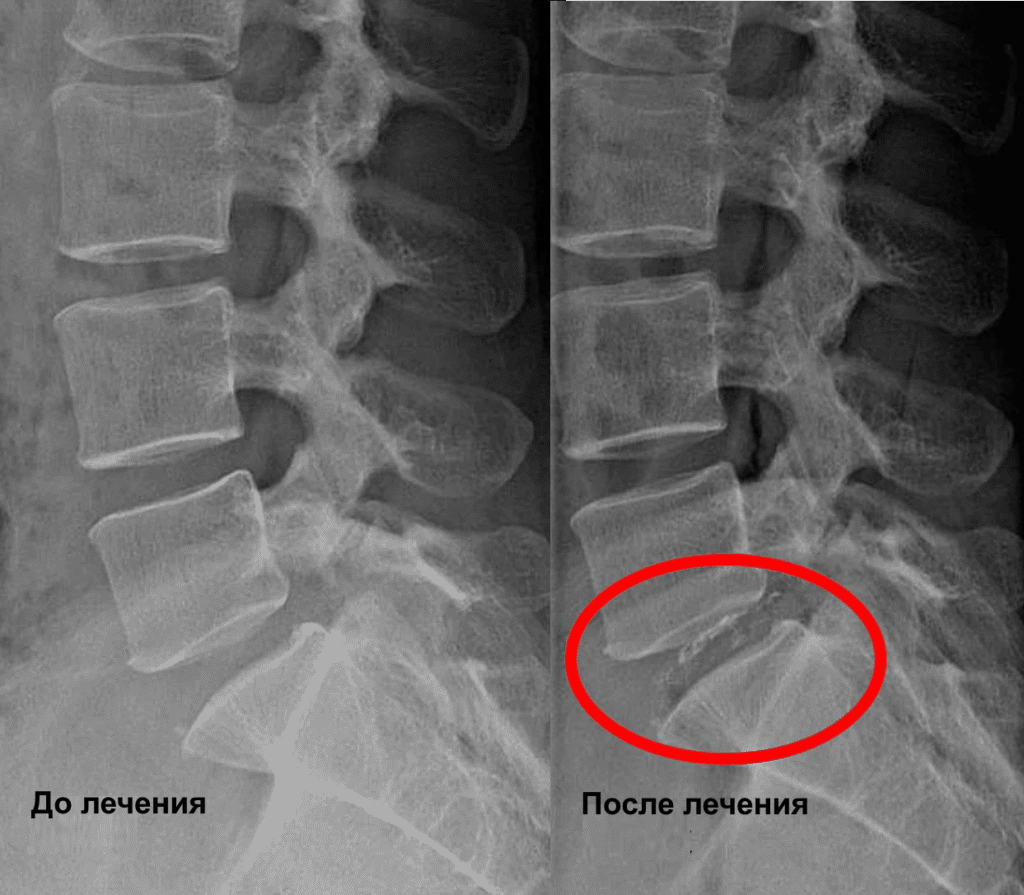

По данным МРТ и осмотра пациентки выявлена межпозвоночная грыжа диска L5/S1.

Проведена селлгель-терапия на диске L5/S1.